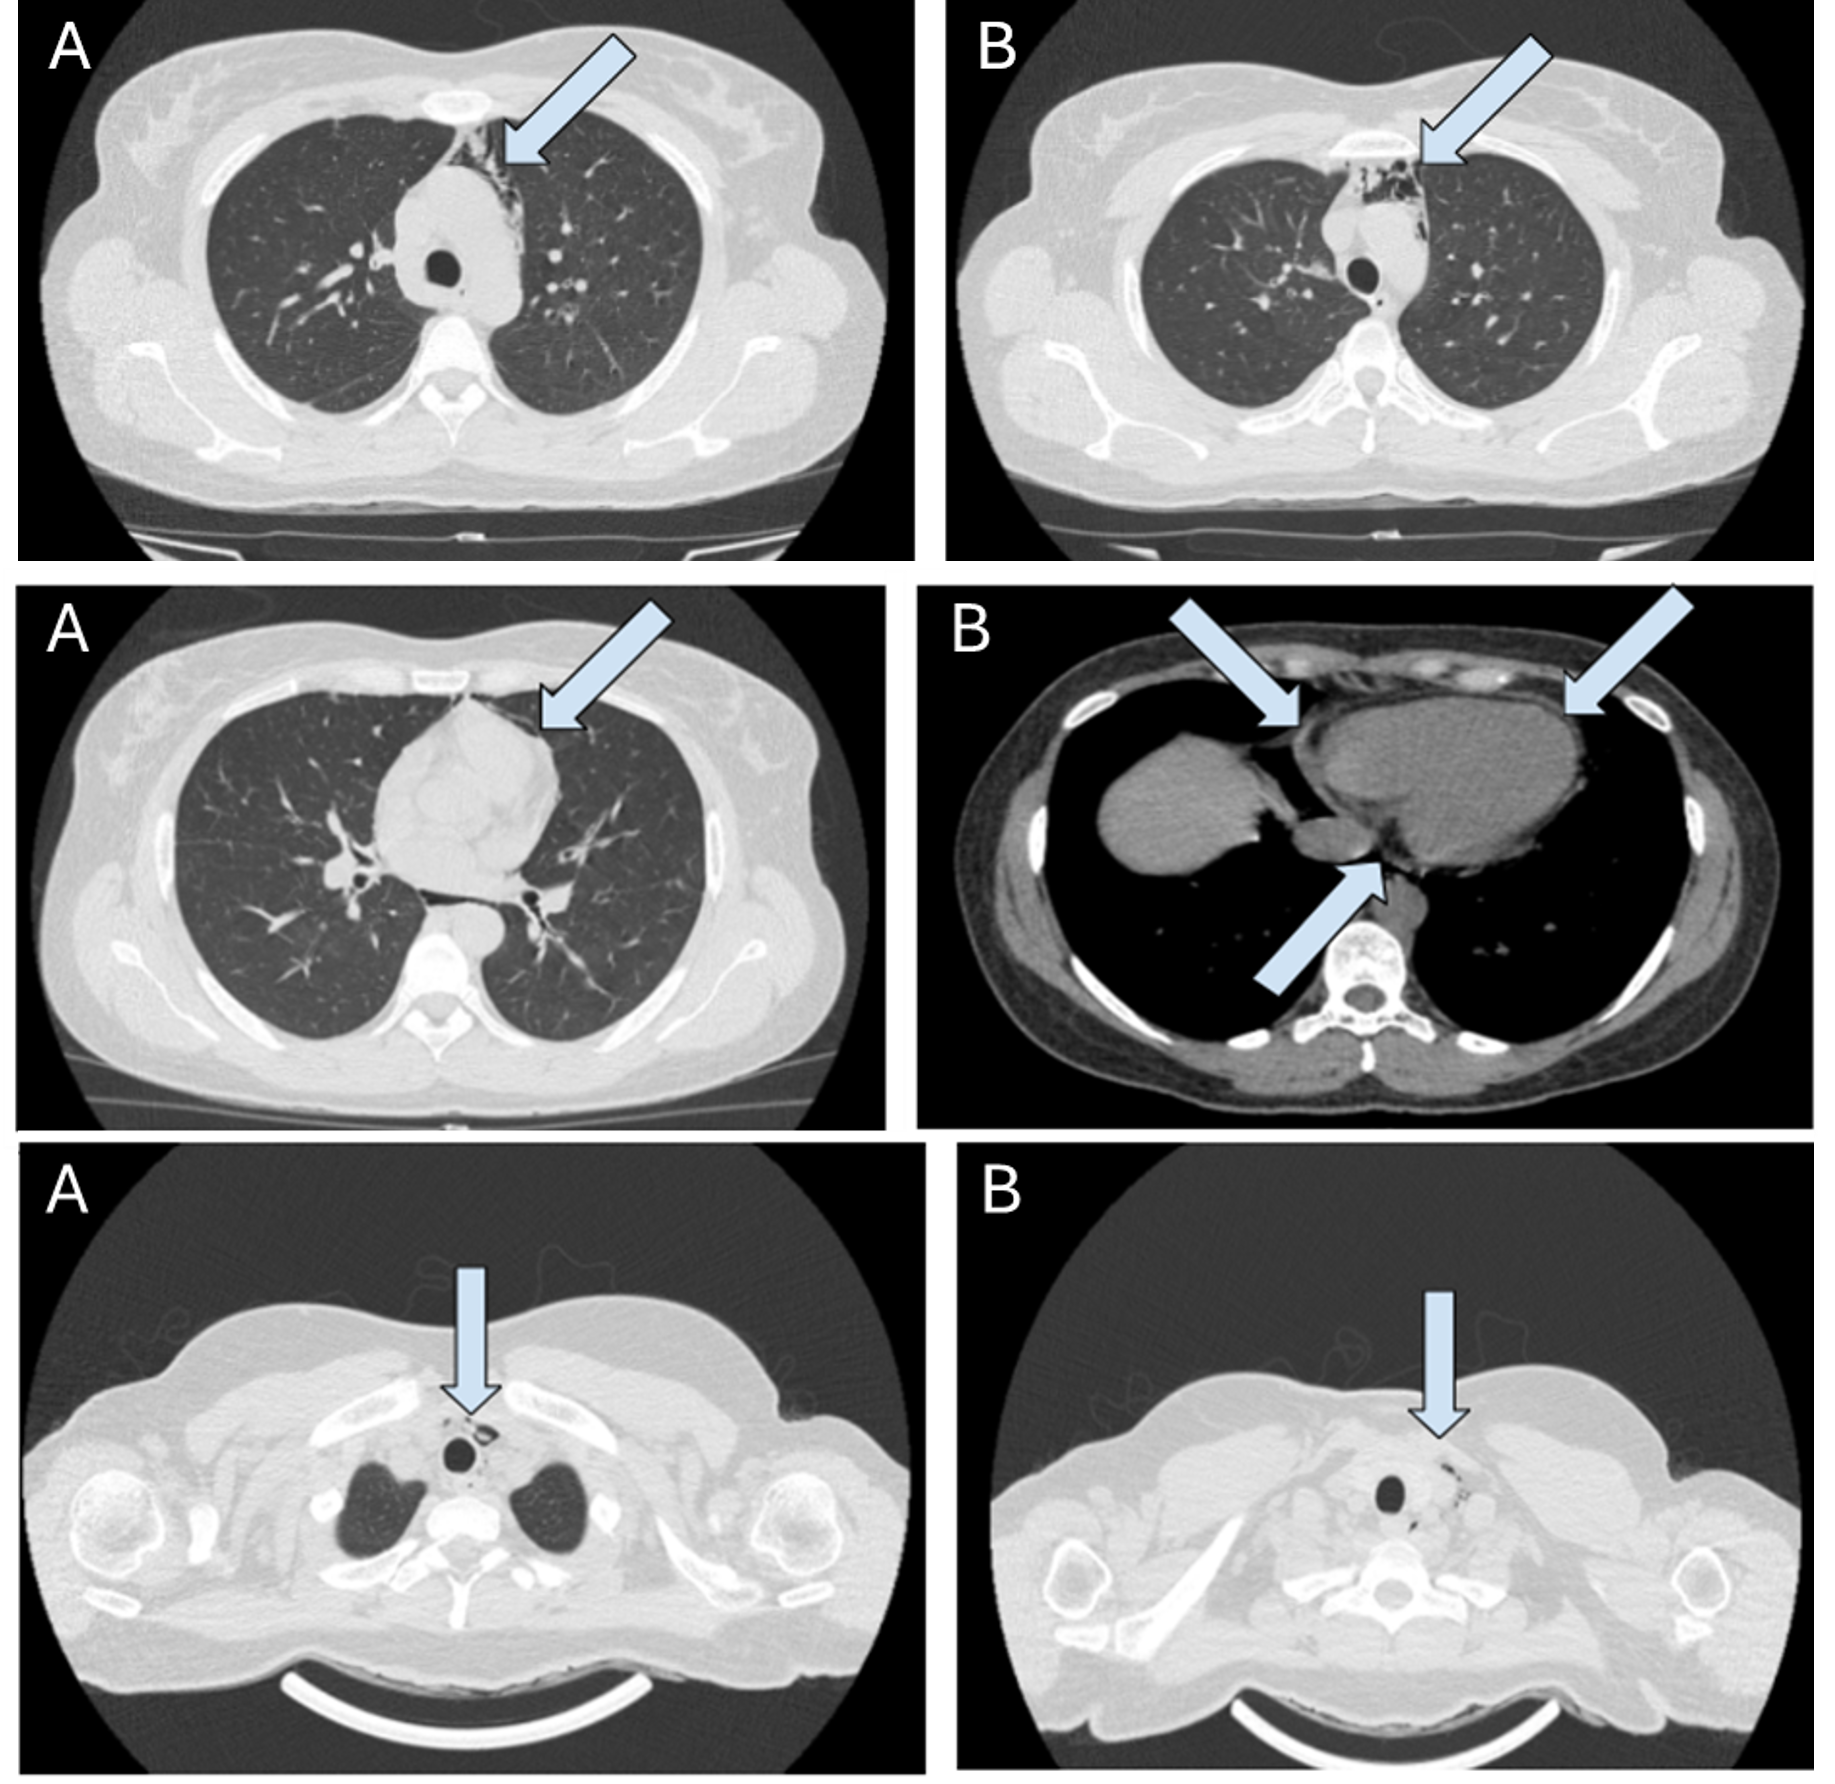

The Challenge of Urogenital Tuberculosis Diagnosis in Elderly Patients

Carolina Seabra, Ana Filipa Silva, Raquel Duro, André Paupério, Vitor Fagundes